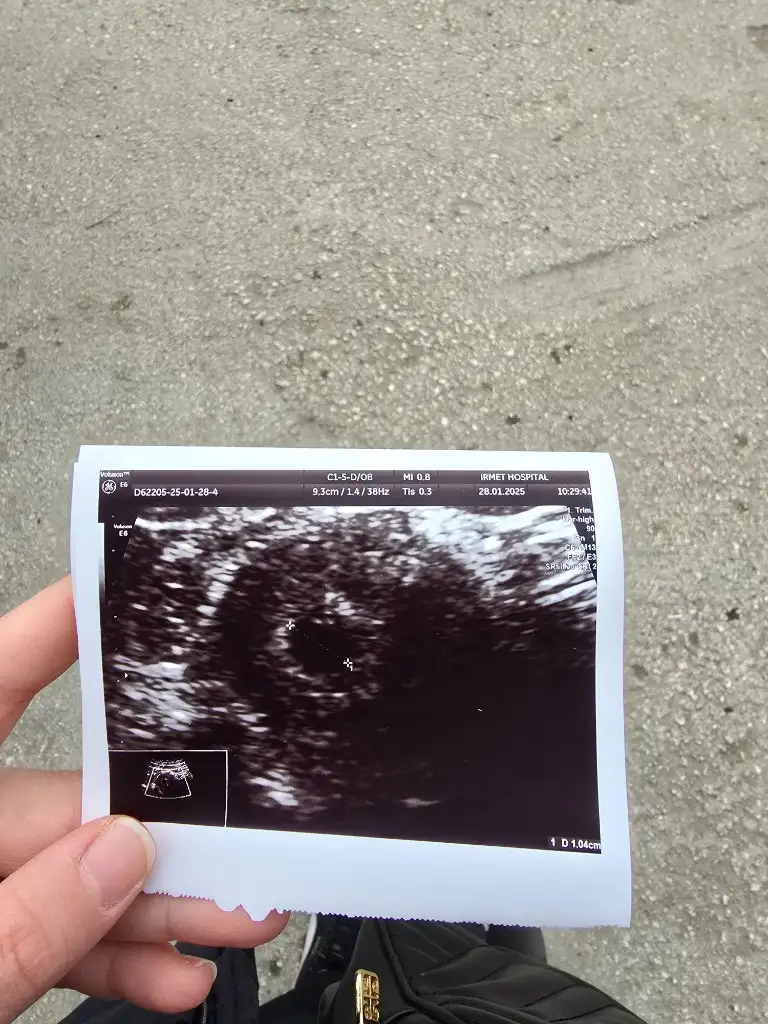

Merhaba sat 25 Aralık

20 ocakta 330 betahcg (tesadüfen acilde öğrendim )

22 ocakta 777 betahcg çıktı

Daha da gerek yok dedi bu değerden tam 1 hafta sonra salı günü doktorum bakmaya gel dedi kadın doğuma kese için

28 ocakta keseyi gördüm .

6 şubatta Allah izin verirse kalp atışı duymaya gideceğiz eğer yeterince büyümüşse tabi

Yani kese için gittiğim gün 6000 i geçmişti betahcg 2 kat yaparsak en az

Senin nasıl durum baştan beri nasıl öğrendin değerlerin kaçtı

Eklentiler

• 20250128_112033.webp

73,2 KB · Görüntüleme: 856